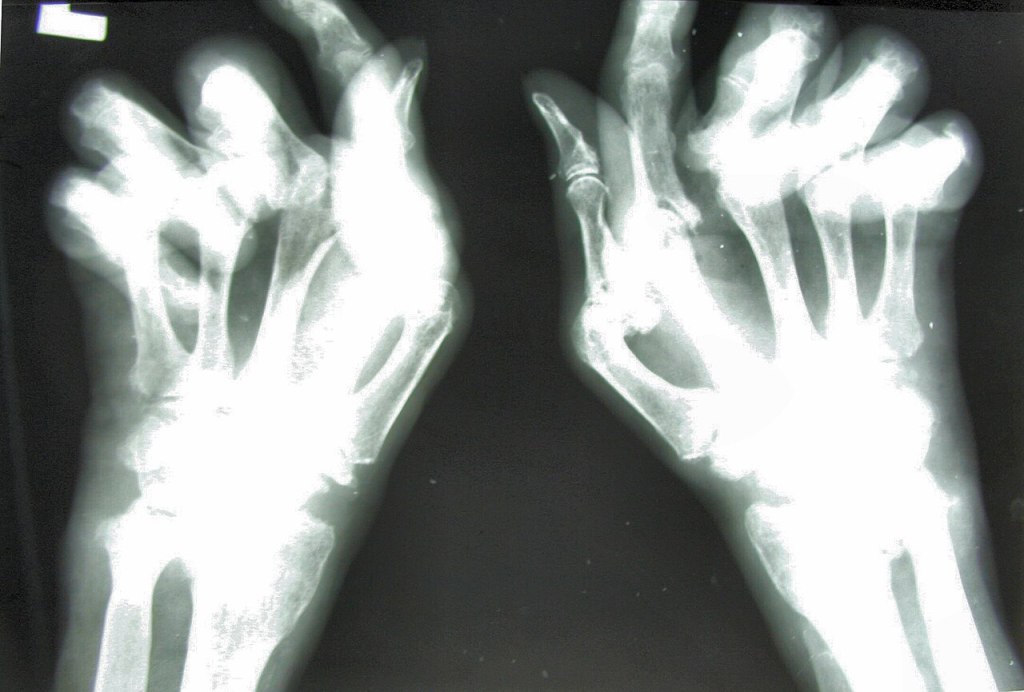

RZS to przewlekły, postępujący proces zapalny, dotyczący stawów, przede wszystkim drobnych stawów rąk i stóp. Następnie obejmuje coraz większe stawy. Choroba rozpoczyna się w błonie maziowej. Prowadzi do niszczenia tkanek stawowych, zniekształceń i upośledzenia funkcji stawów.

Nacieki zapalne w błonie maziowej prowadzą także do aktywacji enzymów lizosomalnych, które powodują destrukcję kości, co w badaniu rtg widzimy w postaci geod, nadżerek, osteoporozy. Uszkodzeniu ulega również aparat więzadłowy stawów.

- ulnaryzacja w stawie nadgarstkowym,

- podwichnięcia stawów,

- zniekształcenia typu: łabędziej szyjki, butonierki, zetki w stawach palców.